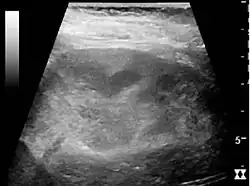

Acute pyelonephritis with increased cortical echogenicity and blurred delineation of the upper pole[20]

Ultrasound findings that indicate pyelonephritis are enlargement of the kidney, edema in the renal sinus or parenchyma, bleeding, loss of corticomedullary differentiation, abscess formation, or an areas of poor blood flow on doppler ultrasound.[21] However, ultrasound findings are seen in only 20–24% of people with pyelonephritis.[21]